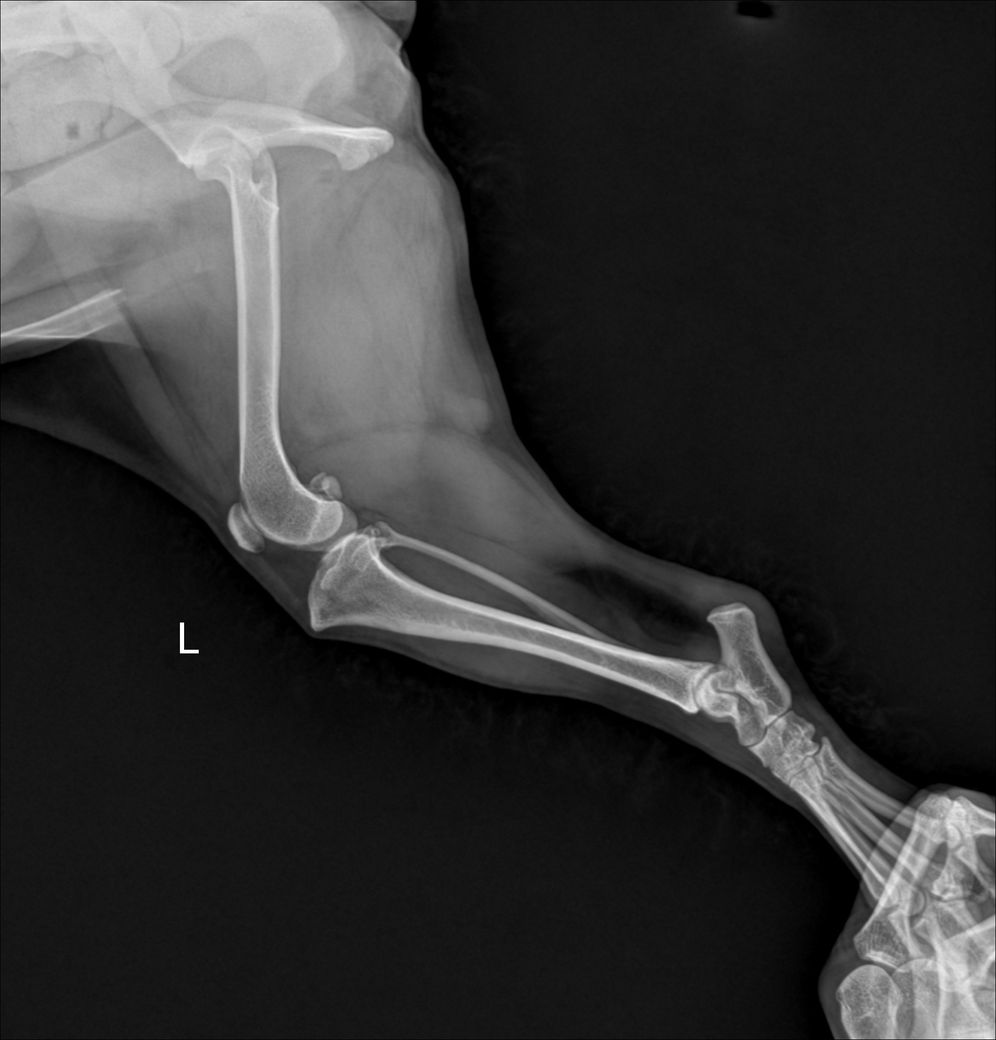

제시된 사진에서는 우측 슬과절 관절낭의 종창 즉, 물이 찬 현상이 있습니다. 이런 현상이 일어나는 원인에는 인대의 문제일 수도 있고, 면역계통의 문제일 수도 있습니다. 특히 이런 물이 찬 상태는 개에서는 십자인대가 손상이 있을때 나타나는 주요 현상으로 스테로이드와 같은 소염작용이 있는 약물을 투약하면 일시적으로 개선될 수 있습니다. 다만 십자인대가 점차 뻣뻣해지면서 향후 십자인대 단열이 발생할 가능성이 높아지니 TPL을 낮추는 수술을 선행적으로 해줄 필요가 있습니다.

사진상에서 실제 좌측에 비해 우측의 TPL이 증가한 양상이 명확하게 관찰되니 주치의와 상담 후 TPLO 고려하시기 바랍니다. ㅈ